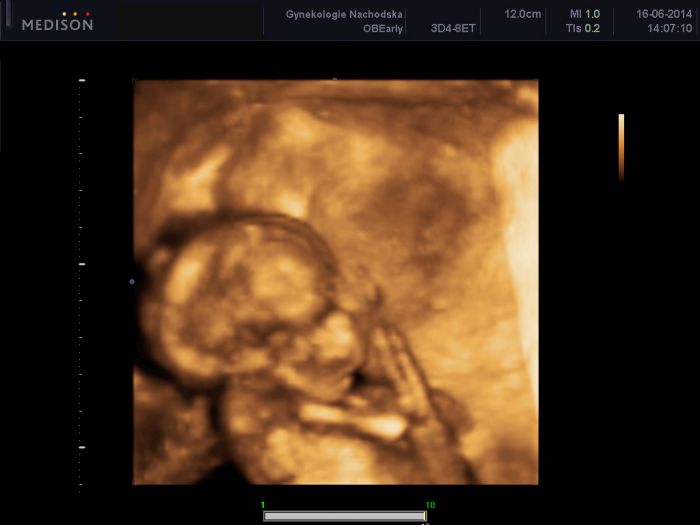

Ahoj holky, přikládám foto z minulého týdne :) utz ve 21+2, malá hodně zlobila takže se nám moc fotek nepodařilo, ale aspoň něco :) jinak je naprosto v pořádku a akční, oblíbená poloha na bříšku s kolinkama pod sebou:) všem přeji pohodove tehulkovani a jen dobre zpravicky :) hezkou středu, papa

Ahoj holky :-). Jeee Tomáška už máme ve 4d nebo co to je za formát. :-) to je super. :-) hoví si tam moc pekne a malá od Míšky teda si taky umí pohovět. :-D je to klabý. Já mám ze včera taky tak přiložím. Též je to z 21+1 ale doktor byl dost nemocný a tak jsem ho nechtěla otravovat lepší fotkou. Zkusil to vzít a já řekla beru. :-D takze tam není ani celej. Můj přítel říkal ,že už má nahoře vlasy :-D:-D:-D takový číro . Jestli je to pravda nevím ,ale všimla si toho i kamarádka. Že to vypadá jak když má už vlasy. :-D jinak ten můj jeník je prostě hodnej. Skoro o něm nevím. Asi ticho před bouři. :-D